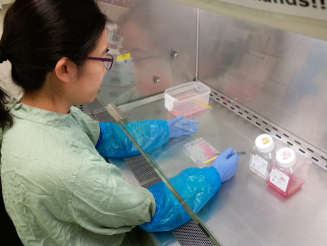

由於過往利用細胞培養技術或實驗動物不能完全真實地呈現人類感染嚴重呼吸道病毒時的情況,香港大學病理學系黎國思教授以及公共衞生學院的陳志偉博士、陳韻怡博士、潘烈文教授及裴偉士教授於二零零五年共同研發「人類呼吸道外植體培養系統」,旨在為尋找以實驗室為本的方法研究嚴重呼吸道病毒感染,同時亦能更真實地反映疾病的機制及用於治療人類時的成效。

外植體培養系統在獲得道德許可的情況下,利用瑪麗醫院丟棄的呼吸道組織作研究。經過八個多月的優化後,系統獲世界衛生組織列為研究動物流感病毒感染大流行風險評估的模型,同時亦被生物技術公司用於評估潛在的抗病毒化合物。食物及衛生局以及大學教育資助委員會研究資助局提供的資金亦使該系統得以開發、優化和維持。